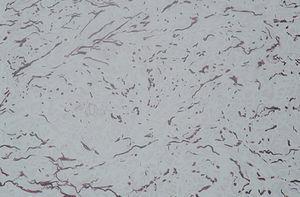

Fig. 4.--Fragmentación y diámetro variable. (Orceína, x20.)

Una niña de 9 años de edad fue remitida por el dermatólogo de zona para valorar lesiones ungueales de 2 años de evolución. En la exploración se apreciaban estriaciones longitudinales en las veinte uñas (fig. 1) que fueron diagnosticadas de traquioniquia. También se observó flacidez e hiperlaxitud localizada exclusivamente en la piel de la pared abdominal (fig. 2). La paciente no había tenido ningún proceso inflamatorio en esta zona ni había padecido episodio febril de marcada importancia. Tampoco había precisado tratamiento alguno por ninguna otra enfermedad. Se realizó estudio analítico de hormonas tiroideas, metabolismo férrico, anticuerpos antinucleares (ANA), inmunoglobulinas y complemento y también se efectuó una biopsia cutánea para estudio histológico con la intención de descartar procesos que cursan con hiperelasticidad cutánea, fundamentalmente cutis laxa y las formas de menor expresividad del síndrome de Ehlers-Danlos (tipos II y V). La analítica fue estrictamente normal y en la biopsia se apreció una reducción de las fibras elásticas (fig. 3), con fragmentación de las mismas y gran variación en su diámetro (fig. 4), no se observaron cambios en las fibras de colágeno (fig. 5). Con estos hallazgos el diagnóstico fue de cutis laxa adquirida localizada y traquioniquia. Intentando establecer una etiología, inicialmente nos planteamos la posibilidad de un proceso inflamatorio larvado o cuadros febriles recurrentes, pero finalmente, y ante la ausencia total de datos en la minuciosa anamnesis realizada a la madre, optamos por incluir a la paciente dentro del grupo de cutis laxa idiopáticos.